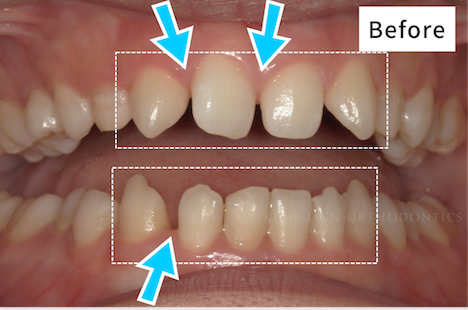

費用 396,000円(税込)

治療期間 10ヶ月

治療内容 マウスピースを用いた歯列矯正

追加処置 IPR

※保険適用外の自由診療となります。

※効果や感じ方には個人差があります。

※マウスピース矯正の主なリスク:

虫歯・歯周病・ブラックトライアングル・歯根吸収・歯肉退縮・1日20時間以上のマウスピース装着が必須・マウスピースにより痛みを感じる可能性・治療中に一時的にかみ合わせに不具合をきたす可能性・リテーナーを最低1年間は1日20時間以上装着、その後徐々に着用時間を減らし、2年目以降は夜間のみの着用推奨。